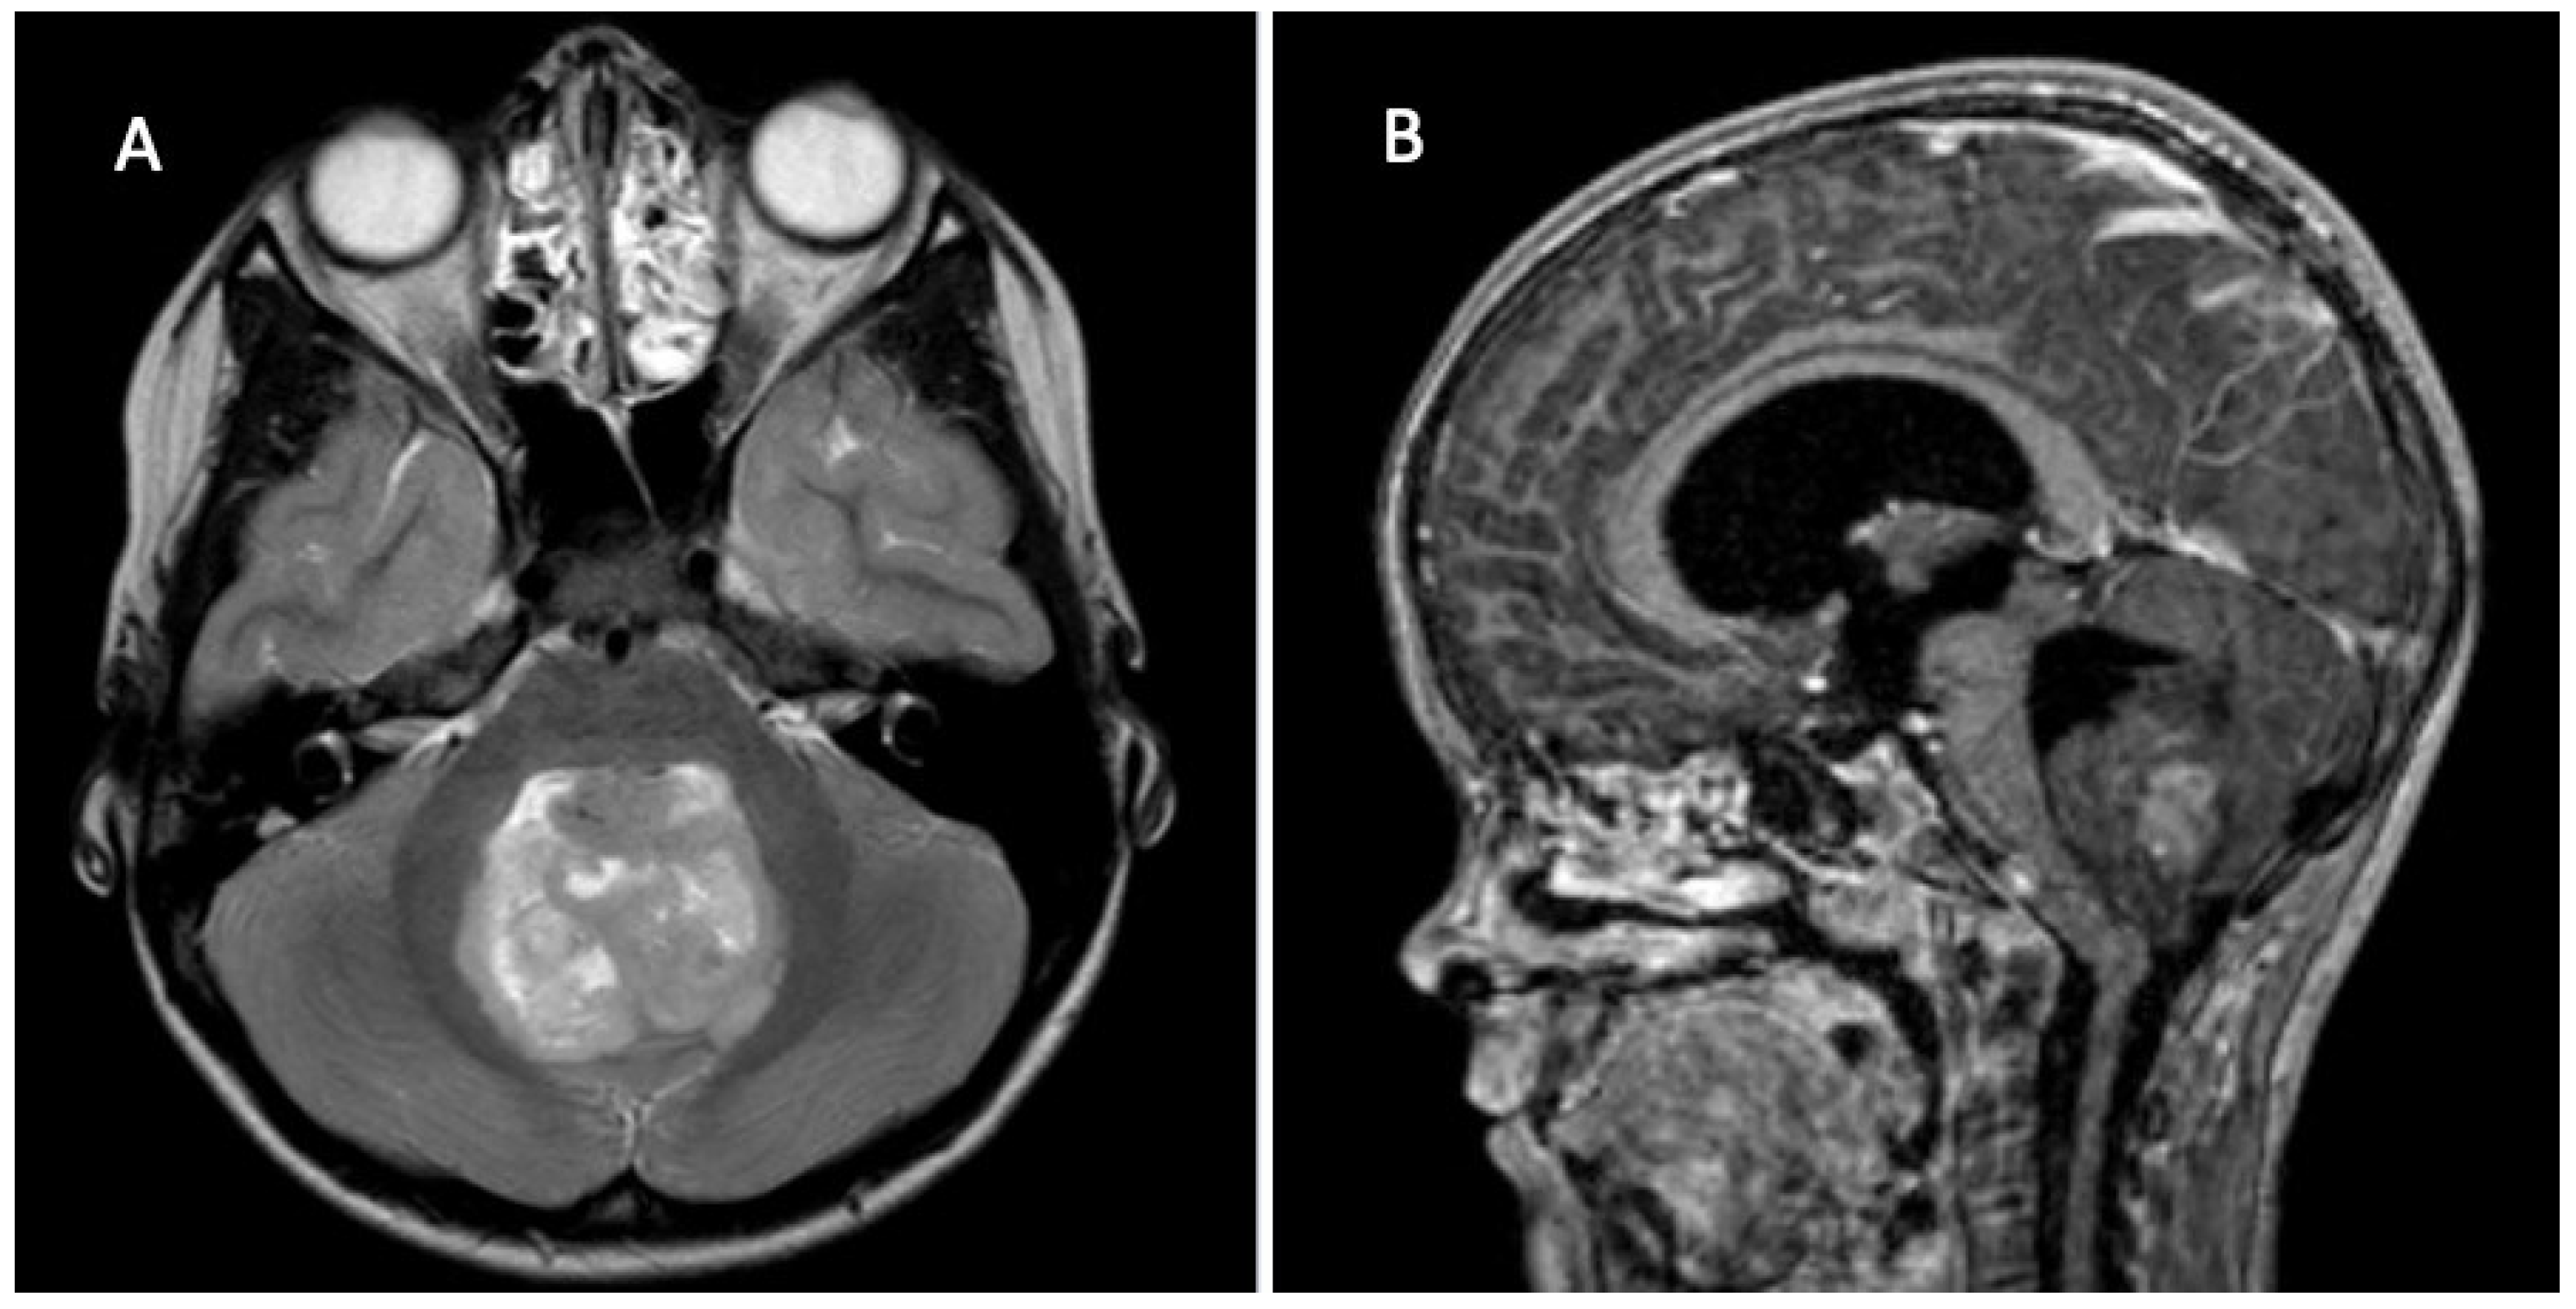

2. Clinical Assessment/Symptoms

3. Diagnostics